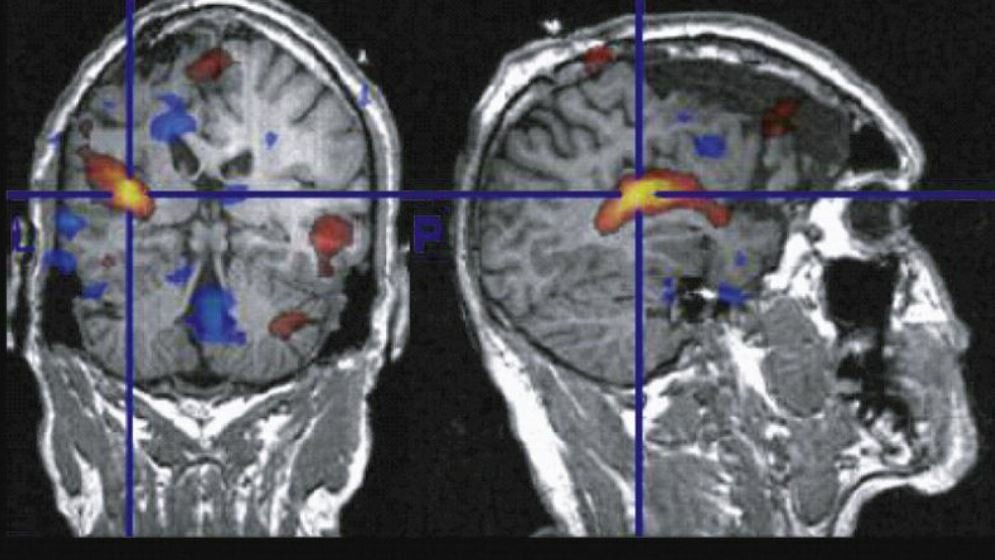

Für die Darstellung anatomischer Strukturen im MRT wird bislang ein sogenanntes graduelles Magnetfeld benötigt. Dieser Gradient muss nach jeder Messung neu aufgebaut werden, was je nach gewünschter Auflösung einige Sekunden bis mehrere Minuten dauert. Schnelle Prozesse lassen sich daher schlecht darstellen. Vor wenigen Jahren hat das Team um Prof. Hennig einen Ansatz entwickelt, bei dem auf das graduelle Magnetfeld verzichtet wird und die MRT-Signale direkt gemessen werden können. Kernstück der Methode ist ein Helm mit bis zu 95 kleinen Empfangsspulen. Das Signal einer Spule kann jeweils dem Hirnbereich direkt unter der Spule zugeordnet werden. „Damit ist es uns gelungen, eine Messung des gesamten Gehirns mit einer Auflösung von drei Millimetern in einer Zehntelsekunde durchzuführen. Von diesem Erfolg waren wir selbst überrascht“, sagt Prof. Hennig.

In dem nun anlaufenden Projekt möchten die Forscher die Strukturen des Gehirns auf zwei Millimeter genau darzustellen. „Das klingt nicht viel, erlaubt aber völlig neue Anwendungsbereiche, etwa die detaillierte Beobachtung des Gehirns nach einem Schlaganfall“, sagt Prof. Hennig. Außerdem möchten die Forscher klären, ob die Methode schnell und präzise genug ist, um damit in Echtzeit Prothesen zu steuern. Bereits heute wird das Verfahren bei Epilepsie-Patienten zur Lokalisierung der Anfallsherde genutzt. Bislang müssen den Patienten dafür in einer neurochirurgischen Operation Elektroden auf der Gehirnoberfläche implantiert werden. „Unsere Messmethode könnte helfen, den Patienten diesen sehr aufwändigen Eingriff in Zukunft zu ersparen“, sagt Prof. Hennig.